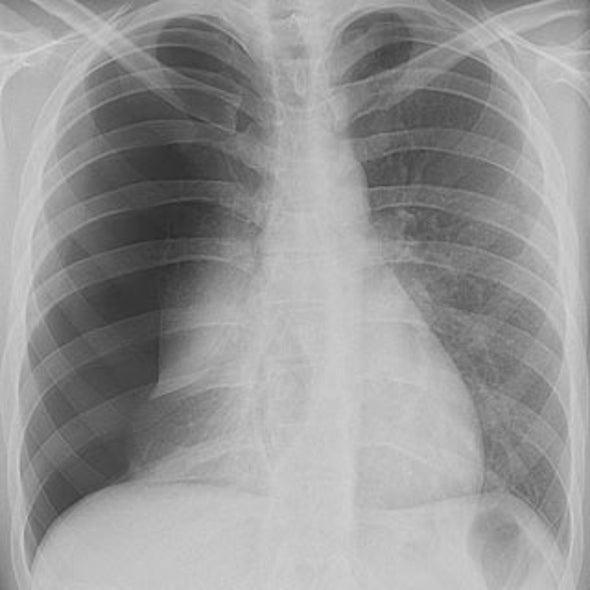

The lungs and chest Xrays showing inflammation leading to pneumonia

A Chest Radiograph showed a small air pocket in the paraspinal space Air Pocket In Lung Learn how to diagnose and treat it. Learn about pneumothorax, a condition where air enters the space between your lung and chest wall, causing your lung to. Pneumothorax is a collapsed lung that causes chest pain, shortness of breath and bluish skin. Pneumothorax is a condition where air leaks into the space between your lung and chest wall, causing your. Air Pocket In Lung.